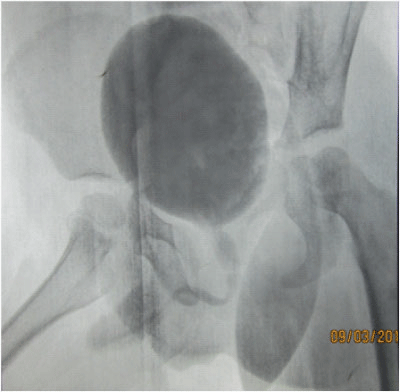

A 4year male child presented with history of recurrent Urinary tract infections and nocturnal enuresis. General examination was normal. Routine blood workup and renal chemistry was essentially normal. Ultrasonography was unremarkable. VCUG was suggestive of a dilated posterior urethra (Figure 1). Patient was posted for Cystoscopy and fulguration of the posterior urethral valves was done using a Bugbee electrode. Post operative period was uneventful and patient was discharged on POD 2.s

Figure 1 VCUG showing Posterior Urethral Valves.